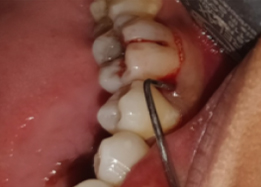

PRE OP Clinical Photograph Measuring Probing Depth